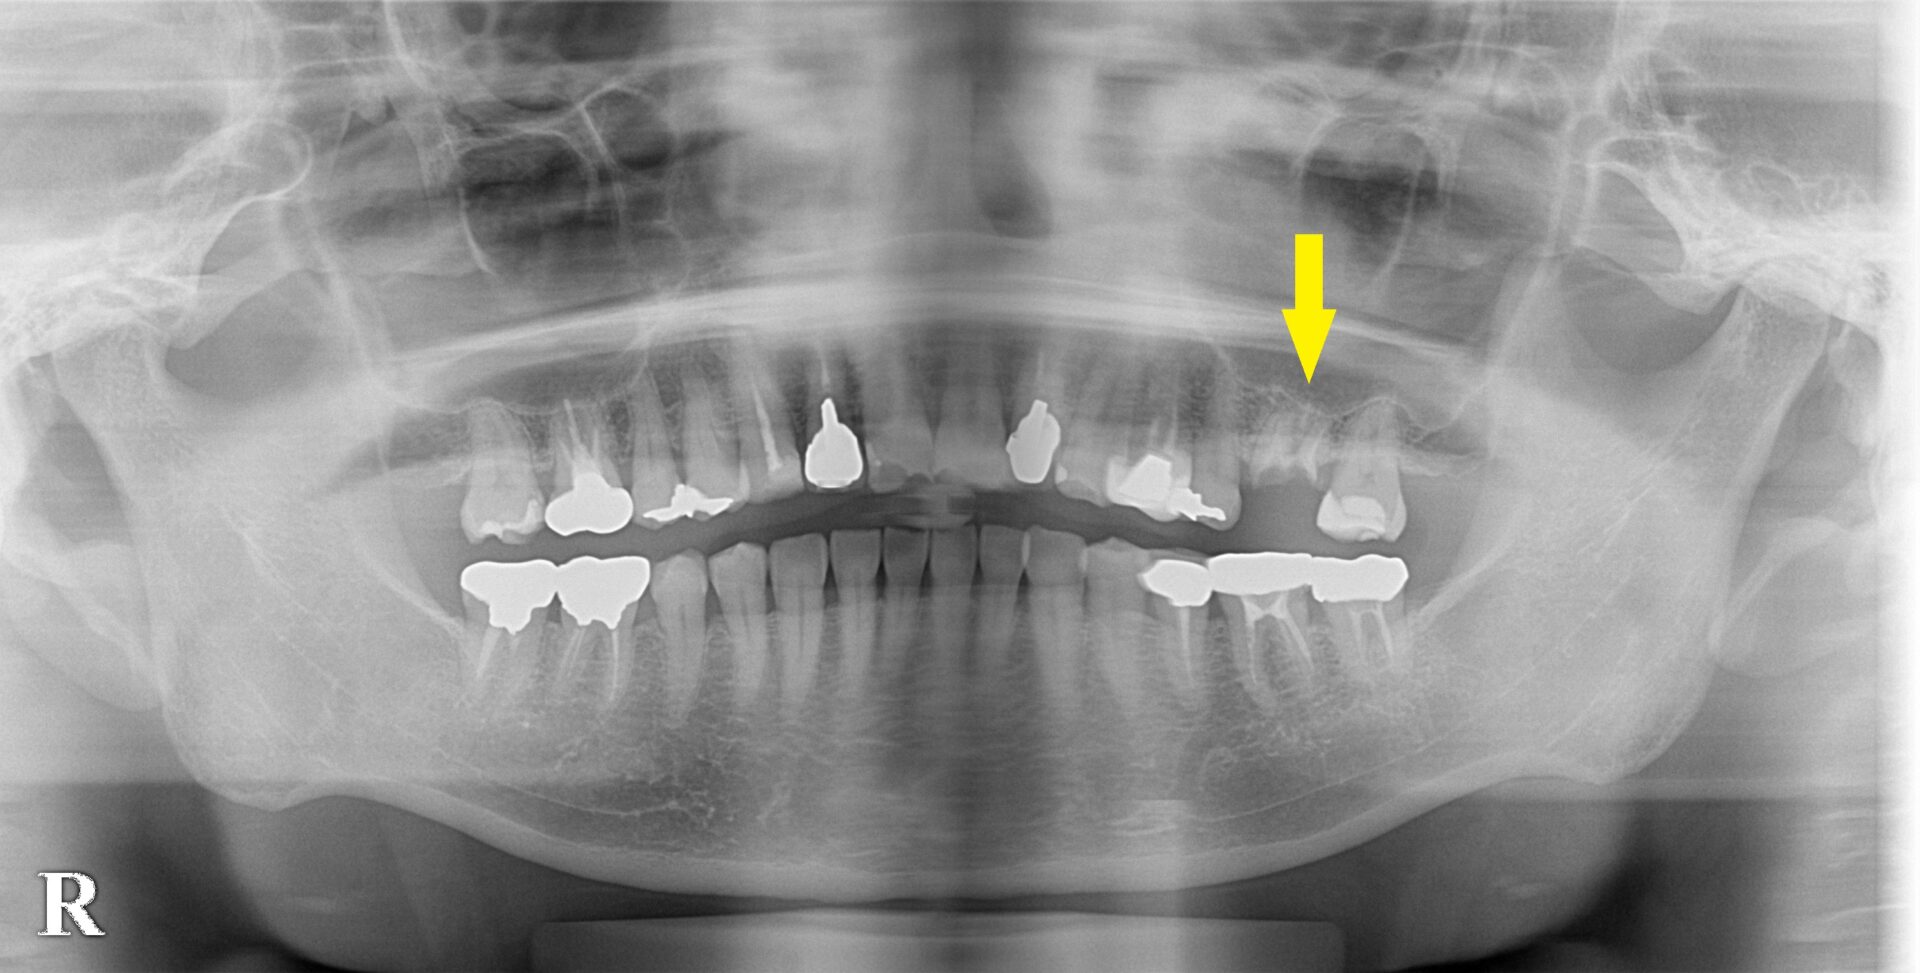

左上顎大臼歯のワイドインプラント症例

左上顎第一大臼歯の冠が外れ、歯が折れてしまった状態でした。

残っているのは歯根部分の先の方のみでしたので、残して差し歯は難しいとお伝えし、抜歯、インプラントをお勧めしました。

まずは抜歯して、数か月治癒を待ってCTを撮影してみると、骨の厚みが4mm程度でした(下の写真中段)。